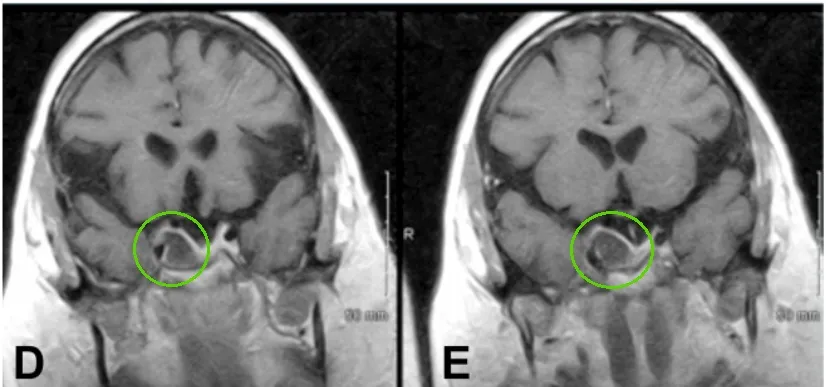

▼术前影像显示肿瘤体积巨大

鉴于肿瘤体积巨大,手术策略采取了分次联合手术入路。

治疗第一部分:此患者属于明确的非功能性垂体腺瘤,首先采用经蝶窦切除术。

▼术后影像显示肿瘤体积明显缩小

治疗第二部分:采用右额开颅术经皮质入路治疗颅内残余肿瘤。

▼术后影像